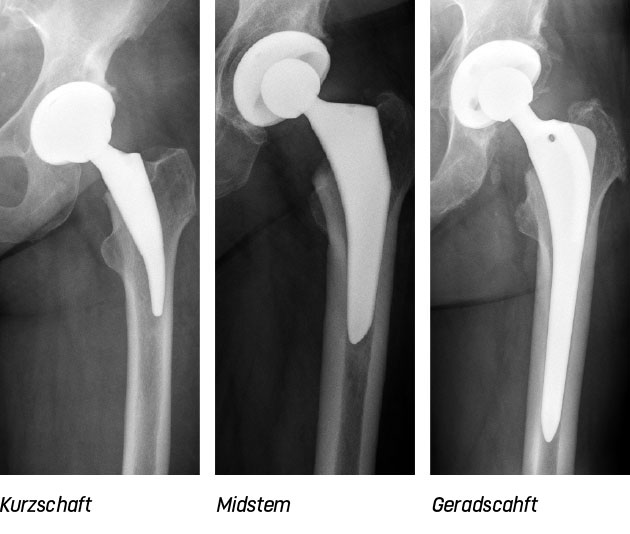

Die Kunst hierbei ist es, diese Besonderheiten zu erkennen und durch die Auswahl des richtigen Implantats diese Anatomie wieder zu rekonstruieren. Zur Verfügung stehen moderne Implantate: Kurzschäfte, Midstems und Geradschäfte (Bild). Auch innerhalb dieser Prothesentypen gibt es vielfältige Variationen in Länge, Breite und Winkel. Ebenso bedingen Knochenqualität und Aktivitätsgrad des Patienten die Prothesenverankerung: Zementiert oder zementfrei.